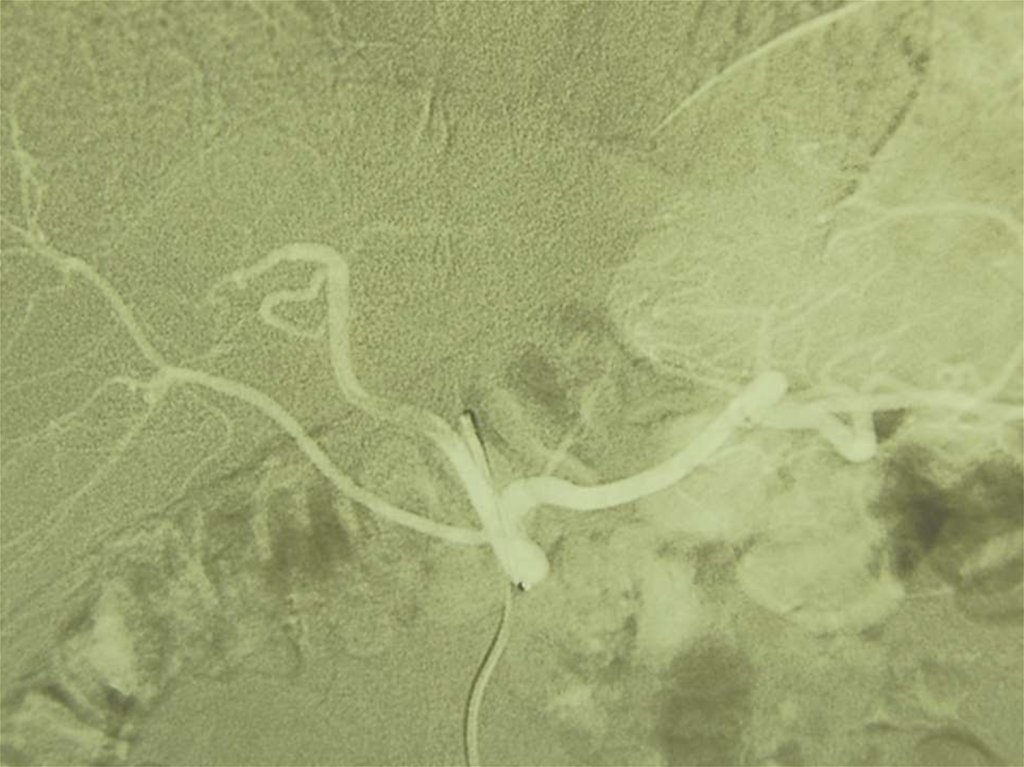

10. Эмболизация ЛЖА у больного с кровотечением при язве желудка

Эммболизация. Производится селективная

катетеризация левой желудочной артерии и

ее эмболизация микроэмболами ( ПВА,

Гидрогель, гемостатическая губка), а также

свободными микроспиралями.